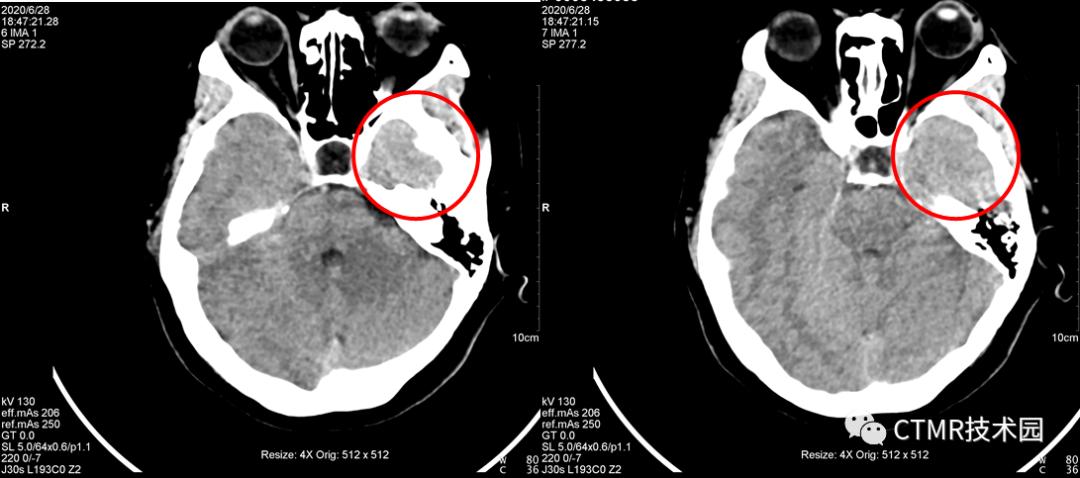

问题2:130kV 配合 1.1 螺距可以吗?

不可以。会出现与暗区相反的结论。即在原来右侧(扫描方向头向足)容易出现暗区,那么用 130kV 配合 1.1 螺距会出现在左侧(扫描方向头向足)容易出现亮区。原来右侧暗区的地方反而正常了。那么经过上面讨论可知,要想用 130kV 也得要配合小点的螺距。

那么如何去除呢?就需要减小螺距,减小到什么程度呢?产生伪影的暗区在 z 轴范围上的距离小于等于螺距乘以探测器宽度的距离。从图像上观察,这个暗区的范围大概是 2~3 层,那么就是 1cm ~ 1.5cm 的范围,那么再结合探测器宽度 64*0.6mm = 3.84cm,那么为了保障预留足够的范围,螺距应当设在稍微比 0.5 大些,那么可以设置 0.5 或 0.55,当然更小的螺距也是可以的,但结合整体扫描时间,还是尽量在没有伪影范围内适当大些。

为什么要这么设置螺距呢?为的就是让球管从伪影侧再曝光一次,以弥补射线硬化而产生的伪影。这样重建出来的图像就会削减本文一开始所说的伪影。